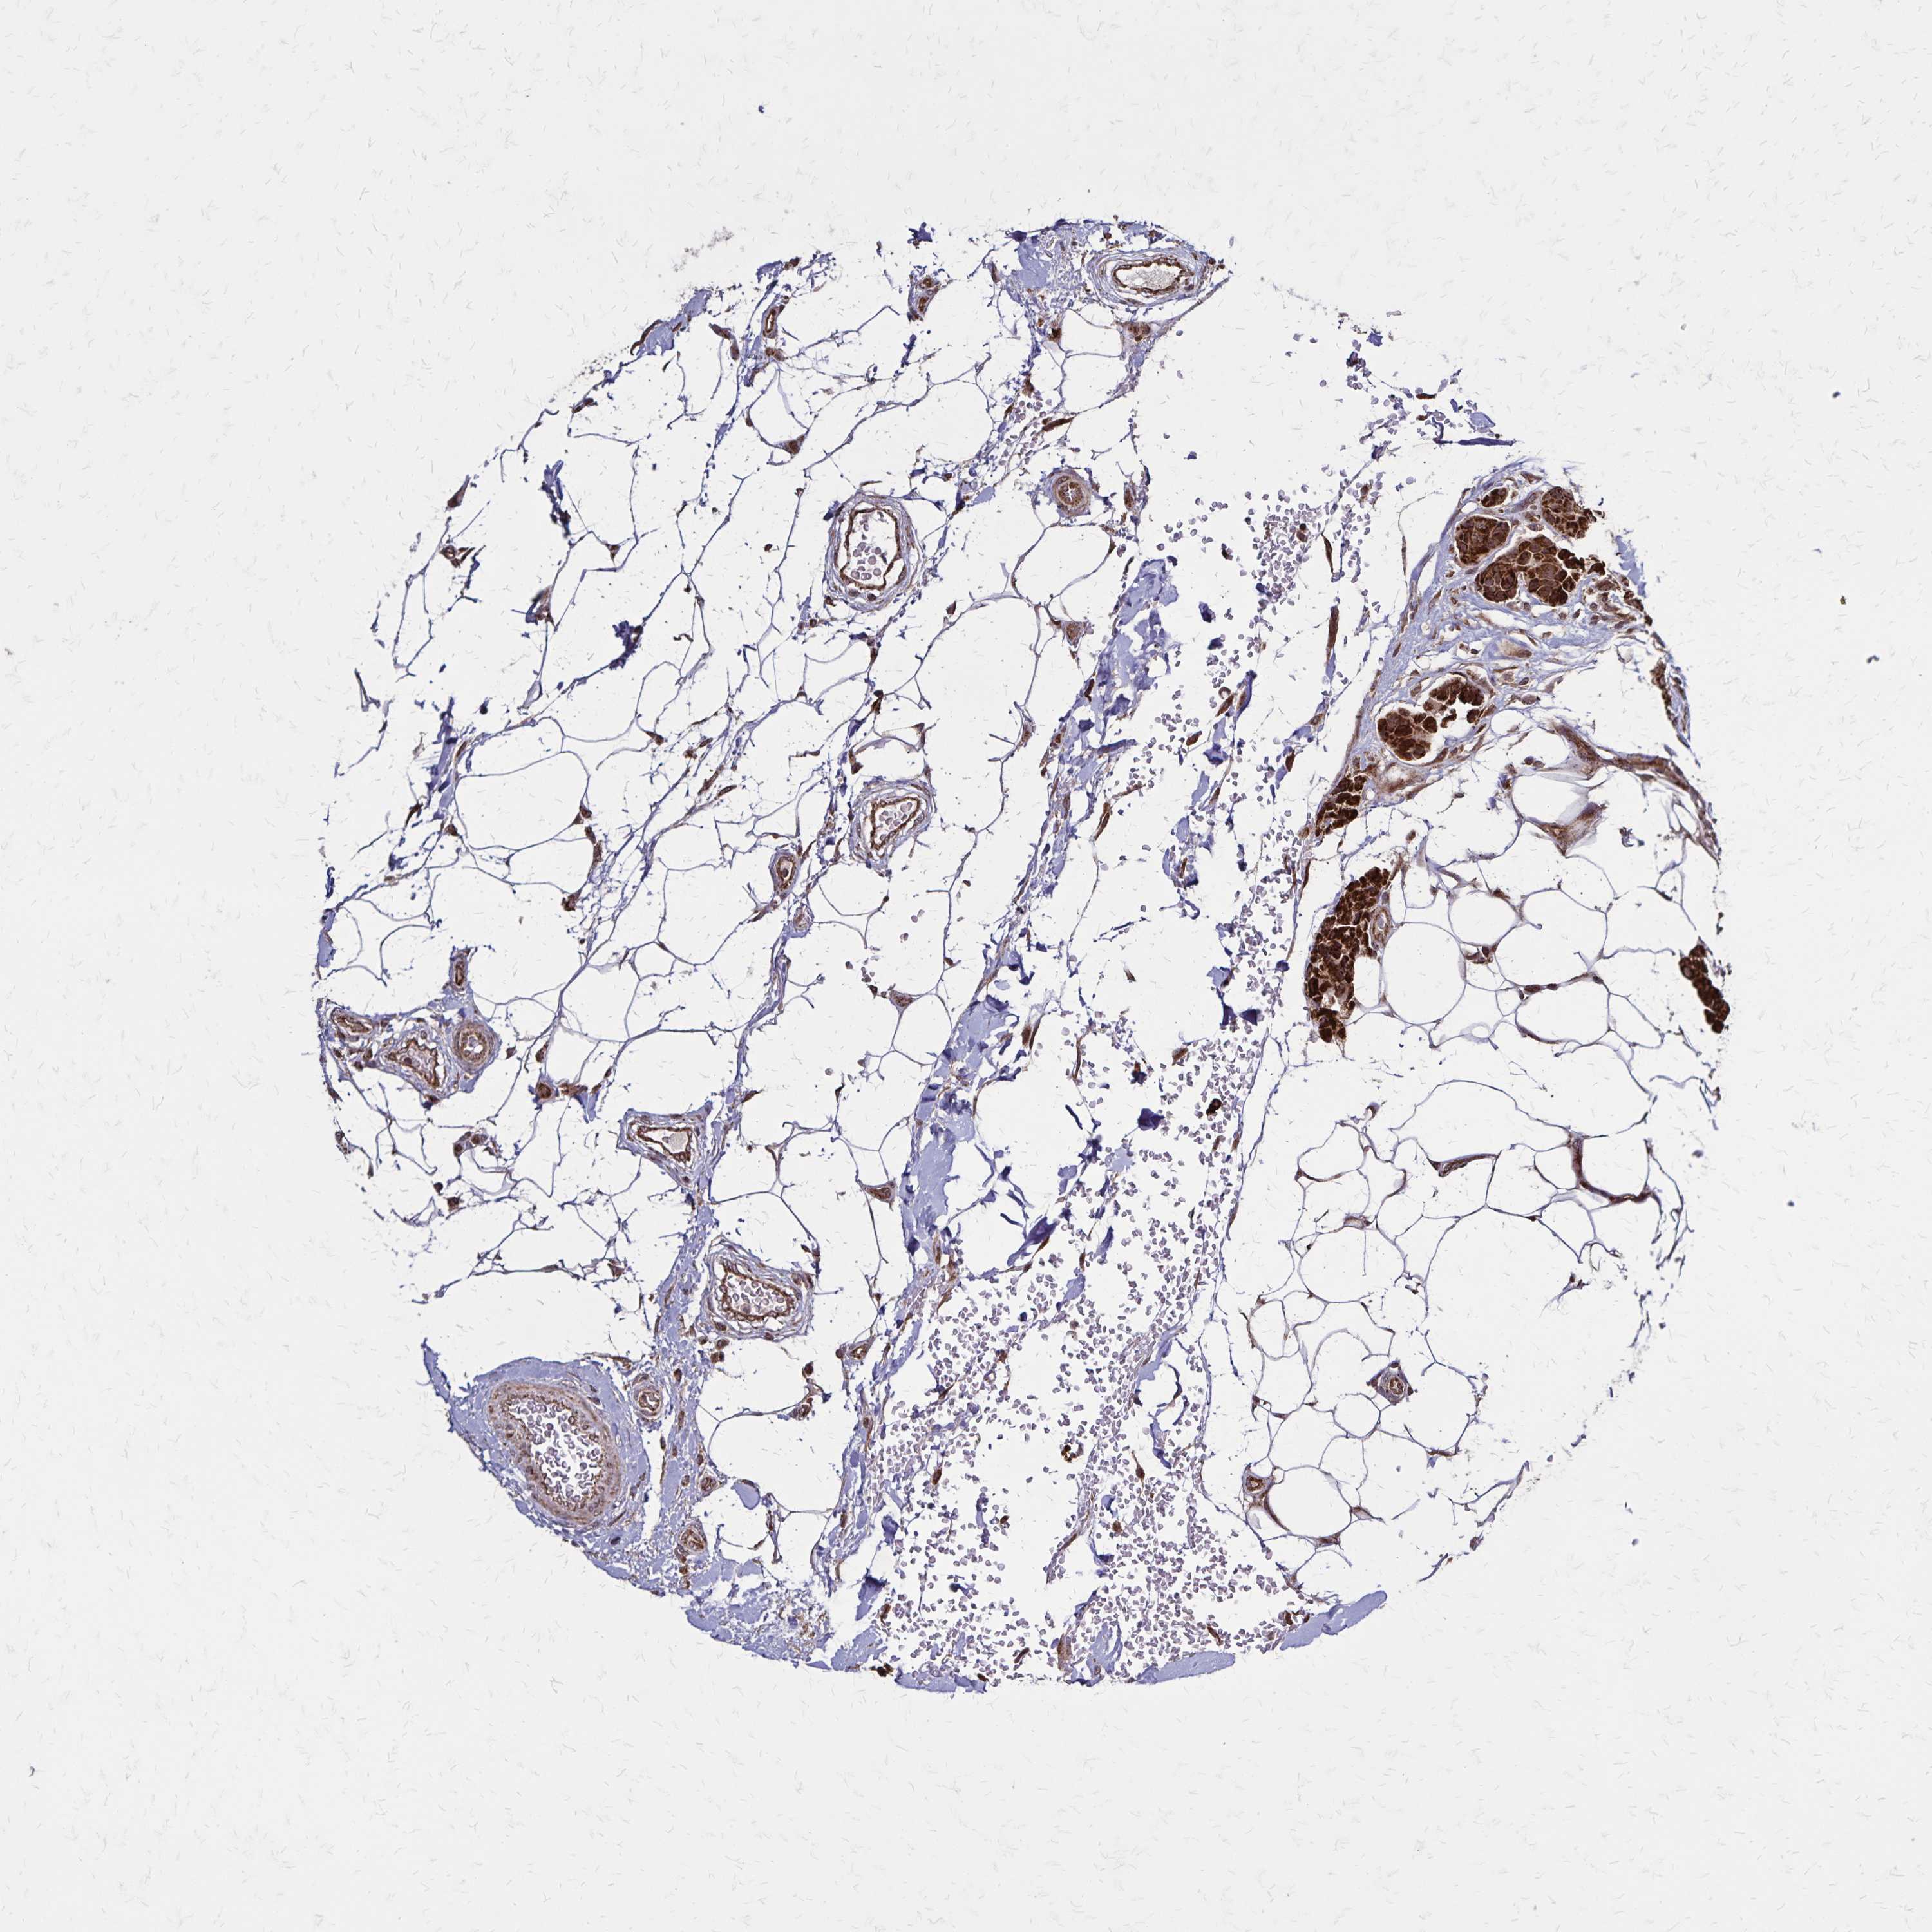

CANCER BREAST CANCER Show tissue menu

BRCA TCGA BRCA VALIDATION PROTEIN EXPRESSION

ANTIBODIES

AND

VALIDATION